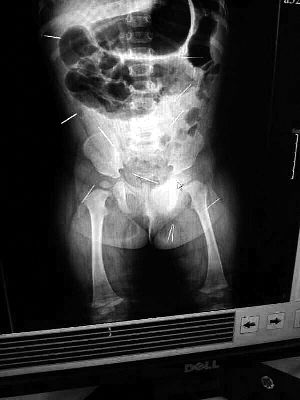

目前體內的12根鋼針多分布在孩子的臀部,一根在腹部,其余3根在胸腔附近,其中一根很接近心臟

北京晨報記者了解到,目前體內的12根鋼針多分布在孩子的臀部,一根在腹部,其余3根在胸腔附近,其中一根很接近心臟。“因為孩子太小,醫生們害怕取針的時候對她造成傷害,在胸腔附近的3針可能會威脅她的生命”。